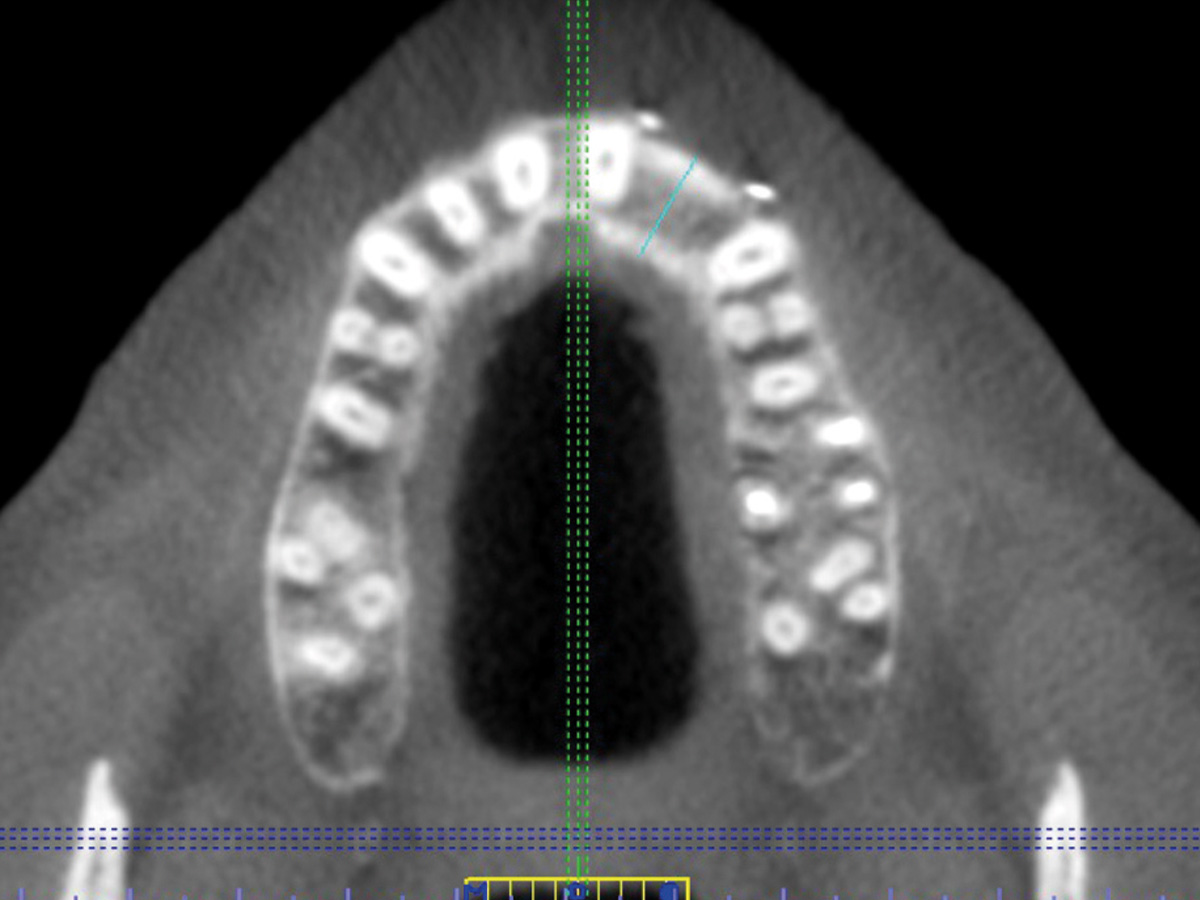

Abbildung 2

Der Defekt im DVT, die Restknochenbreite beträgt 5,6 mm.